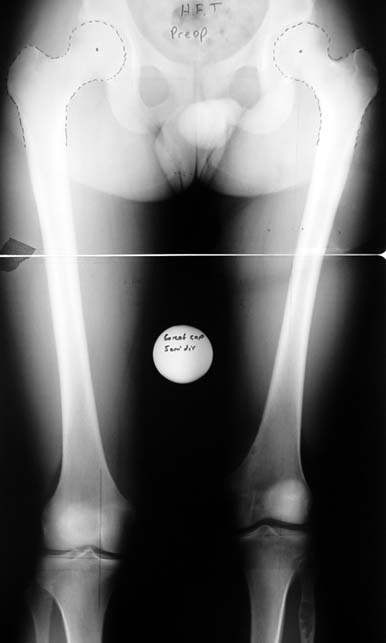

Many patients don’t want to use a shoe support thicker than 2 cm. For length differences between 2 cm and 5 cm, shortening may be considered for tall patients. This can be performed in growing children with a small, minimally invasive, uncomplicated procedure called epiphysiodesis. This means surgical disruption of one or more growth plates. There is a growth plate at the ends of femur, tibia and fibula; this procedure does not halt all growing of the leg. The growing of the longer leg is calculated and halted to allow the shorter leg to catch up.If the procedure is performed at a too early or too late age, the correction may be too much or too little, respectively. Hence, it is important to accurately calculate the most appropriate age for epiphysiodesis. When and at which bone segment epiphysiodesis will be performed shall be calculated by the doctor using different methods such as Gren-Anderson diagram, Moseley curve or Paley’s multiplier method.Epiphysiodesis is not an option for adults because growth plates ar closed. In adults, a bone segment has to be excised surgically in order to shorten the leg. This is usually performed at femur and bone is later fixed with an intramedullary nail. The biggest advantage of this system is that it acutely provides limb length equality for discrepancies less than 5 cm. The common disadvantage of epiphysiodesis and shortening is the shortening of total height of the patient. Because we don’t advice shortening more than 5 cm, height loss can’t be more than 5 cm. For patients who don’t want an epiphysiodesis or shortening operation for length inequalities less than 5 cm, limb lengthening can be preferred in order to equalize the length difference.This can be combined with epiphysiodesis and shortening to decrease a need for another lengthening operation or to decrease the lengthening amount required.